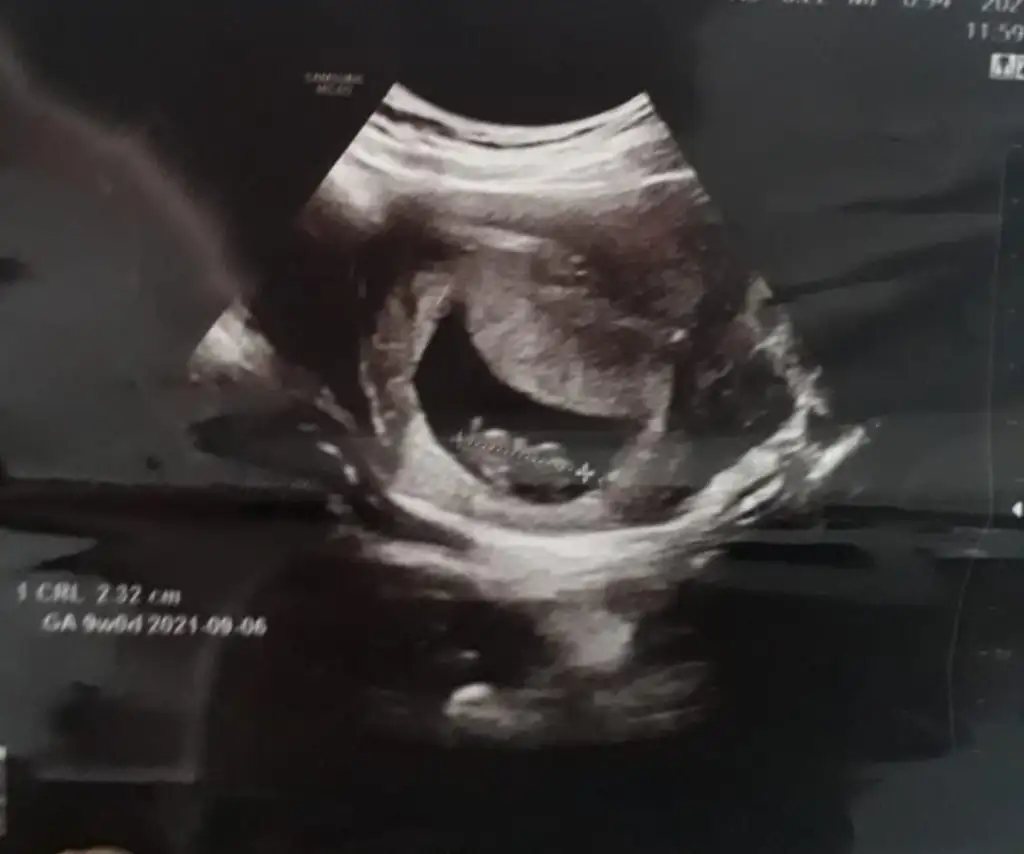

Benimde tahmin edebilir misiniz ilk resim 6 +4 günlük ikinci resim 13 +3

Merhaba bnmde burda 6+2 şuan 9+3 haftalığım çok merak ediyorum bir kızım var bunun cinsiyeti ne olucak diye lütfen bana da söylermisiniz tahmininizi ben hiç anlayamıyorum